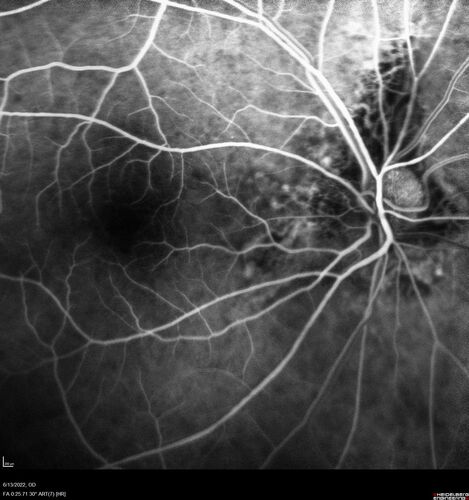

Optic nerve (disc) drusen and choroidal neovascular membrane

85 year old man - The left eye has had poor vision for 7-8 years.  The right eye is OK.  He was in for a checkup and his ophthalmologist noticed a problem and asked him to see retina doctor.

VA OD: Dcc20/25-2 OS: DccCF 1ft

Patient's right eye was treated with Avastin and was dry with one shot.